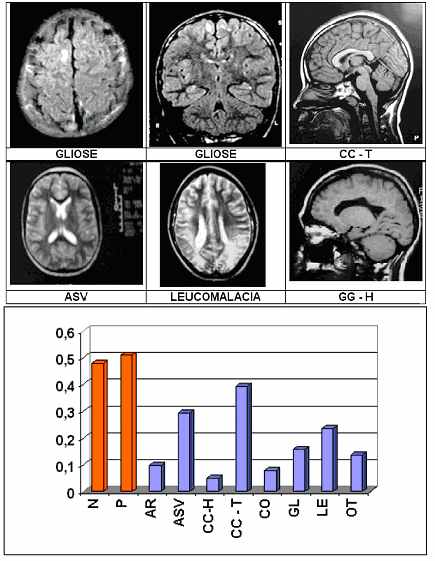

Fig. 2 – Deficiência Mental: As lesões mais frequentes

N – Normais; P – Patológicas; AR – Cisto Arachnoideo; ASV – Assimetria Ventricular; CC-H – Agenesia do Corpo Caloso; CC-T – Adelgassamento do Corpo Caloso; CO – Colpocefalia; GL – Gliose; LE – Leucomalacia; OT – Outras.

a) a RM é normal em 50% dos alunos estudados e que os outros 50% dos alunos apresentam lesões estruturais de vários tipos (Fig. 2);